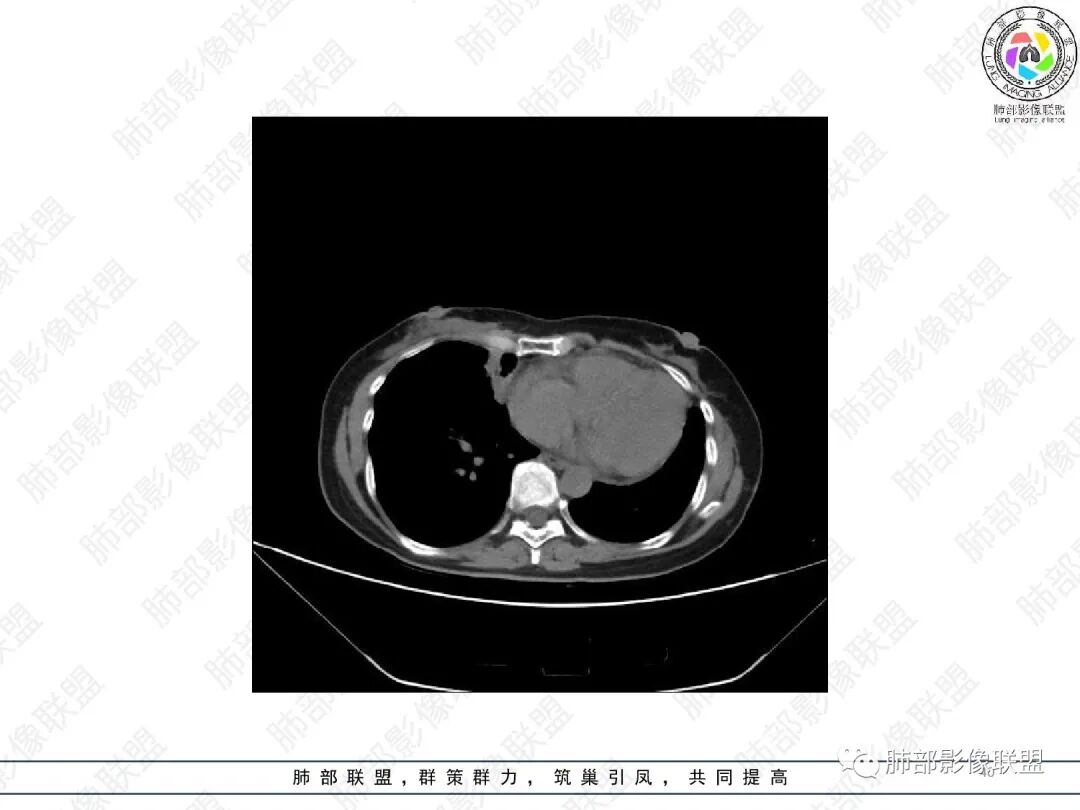

1.中年女性,主因“咳嗽、咳痰半年余”入院,既往史:8年前因左肺病在外院变行左肺叶切除术,诉术后抗结核治疗1年,具体病理等不详。实验室IGE显著增高。

2.胸部CT:右肺上叶及中叶不规则块状影,沿支气管走行方向指套样影,支气阻塞湖嵌塞,腔内可见高密度影。灶周可见磨玻璃,外围见结节影及树芽征。左肺体积缩小,见不规则条索影、胸膜增厚,纵隔牵拉左移。

3.综合分析:结合患者病史及胸部CT主要鉴别ABPA(右肺上叶不规则块影,指套样顺延支气管方向,抗结核治疗1年,肺部病灶仍明显)及继发性肺结核TB(右肺上叶不规则肿块,其可见高密影,边缘模糊,周围卫星灶、树芽征,沿支气管爬行)。

完善气管镜及病理、检验结果(IgE显著增高)等支持ABPA诊断。且给予激素及伊曲康唑治疗后复查胸部CT提示病灶较前吸收,所以诊断明确。